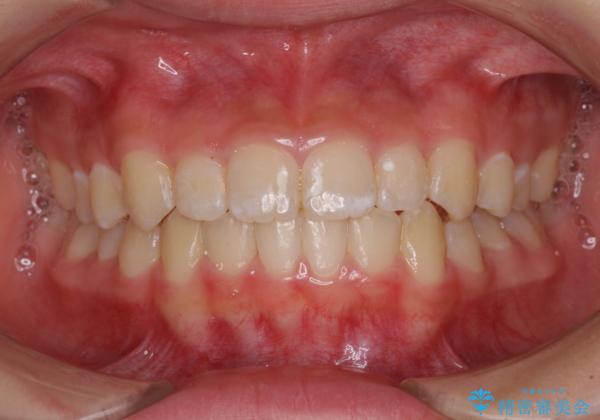

遠方から新幹線で通院 急速拡大装置とインビザラインによる矯正治療

- 小児矯正の頃から診察を行っている患者様です。

上顎骨の幅が下顎骨よりも小さいので、拡大装置により骨幅を広げて上下関係を改善し、その後インビザラインにて歯並びを整えることとしました。

上下の骨幅を改善したことで、スムーズに歯列矯正を行うことができました。

インビザライン治療開始直後に遠方に引っ越しをされたため、通院間隔が長くなり、治療期間が長くなりましたが、しっかりと治療を行うことができました。